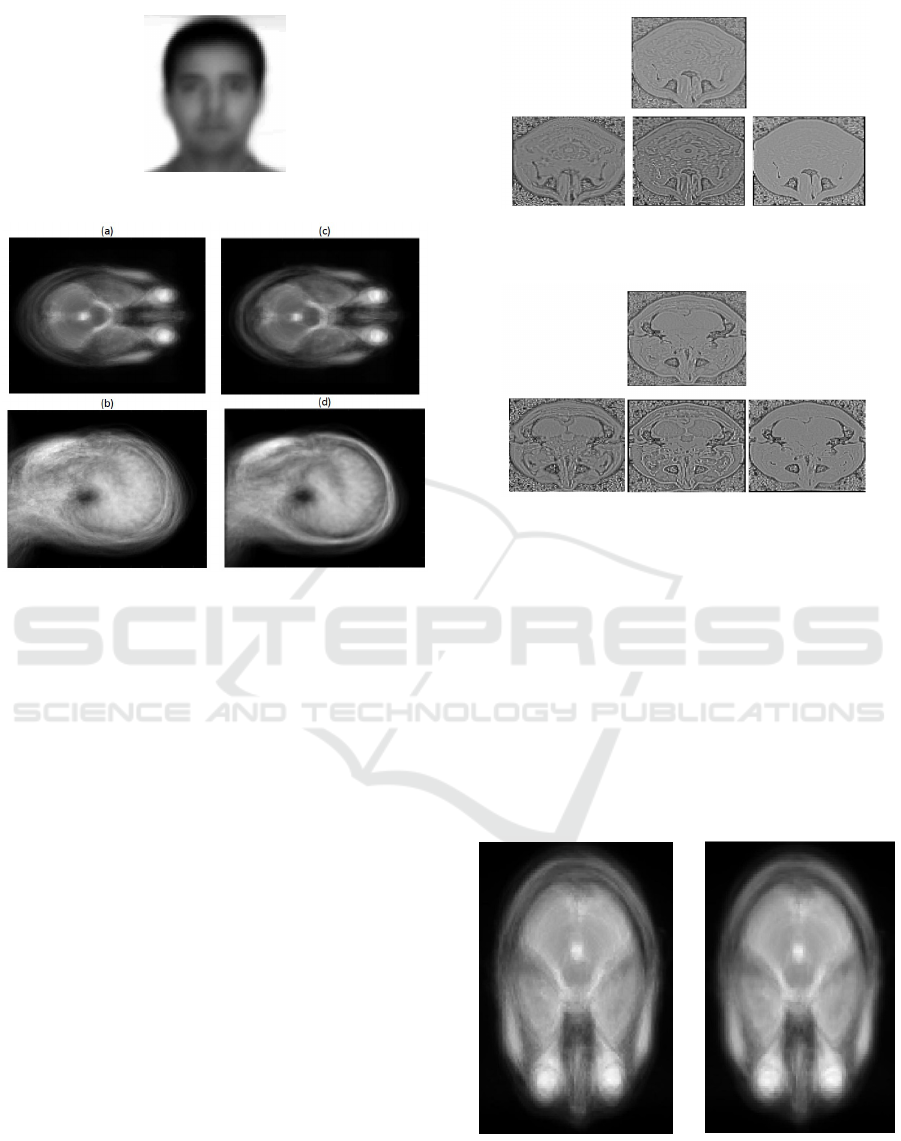

Figure 7: Top Row: T 2 image(left) and the respective quo-

tient image(right), Middle Row: PD image(left) and the

respective quotient image(right), Bottom Row: MRA im-

age(left) and the respective quotient image(right).